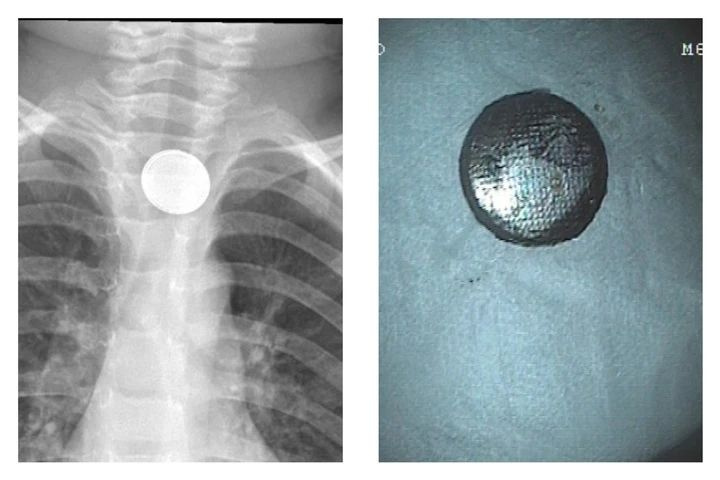

卡在孩子食管里的纽扣电池/受访者供图

“其中最常见的是硬币,大约能占到食管异物的三分之二,不过这些年随着人们支付习惯的改变,硬币在各类异物中的占比略有下降趋势。另外常见的还有纽扣电池、玩具零件、磁性异物、别针、螺丝钉、弹珠、食物骨头、食团、毛发等,其中纽扣电池、磁性异物等高危消化道异物近年来的发生率明显增多,需要特别引起注意。”